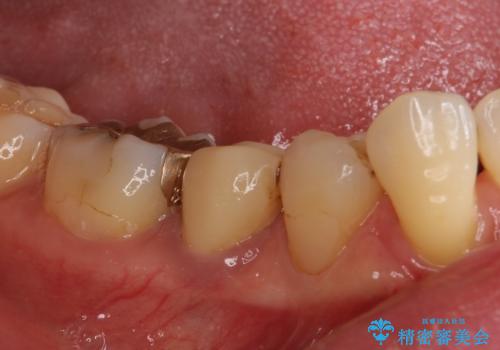

神経が取り除かれた歯であるため、虫歯で歯が失われていく際に痛みを伴わなず、気がついたら大きな穴があいていました。

虫歯を全て除去したうえで新しい土台を築製し、セラミッククラウンにより補綴治療を行うこととしました。

虫歯が歯根深くまで及んでいる場合には歯を部分矯正で引っ張り出したり、歯周外科処置が必要となったりしますが、メインテナンスでレントゲン写真を定期的に撮っていたため、幸いにも矯正や外科処置が必要となる前に補綴治療を行うことができました。